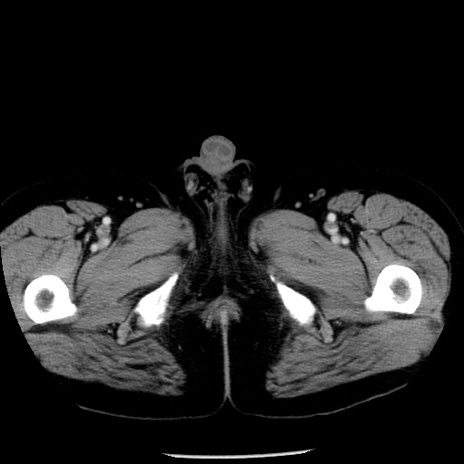

症例29(横断像)

【症例】40歳代男性

【現病歴】2日前から胃痛あり。徐々に周期的な激痛に変化した。本日になっても激痛があるため受診。

【身体所見】意識清明、BT 38-39℃台あり、腹部:膨満、やや硬、右下腹部に圧痛あり。

【データ】WBC 8500、CRP 23.26